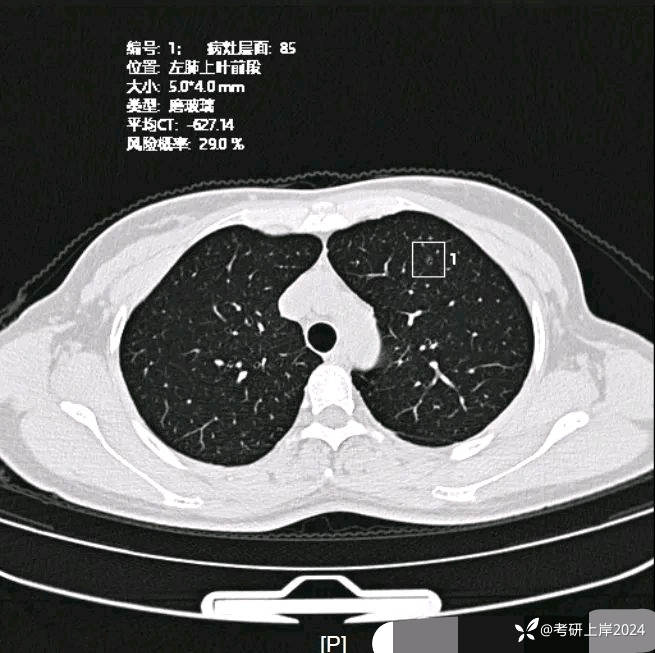

患者最近的检查有AI辅助诊断意见,找出的病灶分别如下:

病灶6:左上叶微小磨玻璃结节,轮廓较清,考虑肺泡上皮增生可能性较大;